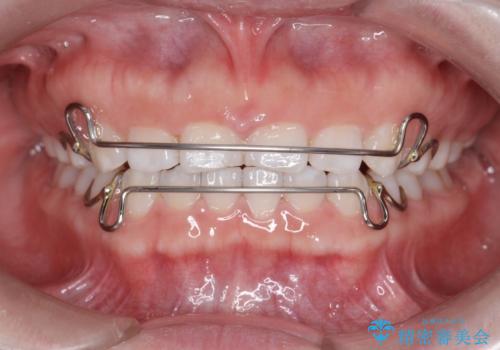

インビザライン 気になるすきっ歯の改善

- 上下顎前歯部の空隙が気になるので治したいと当院にいらっしゃった方の症例です。

非抜歯、インビザラインによる矯正治療により歯と歯の隙間および前歯の上下の隙間を閉じ切りました。